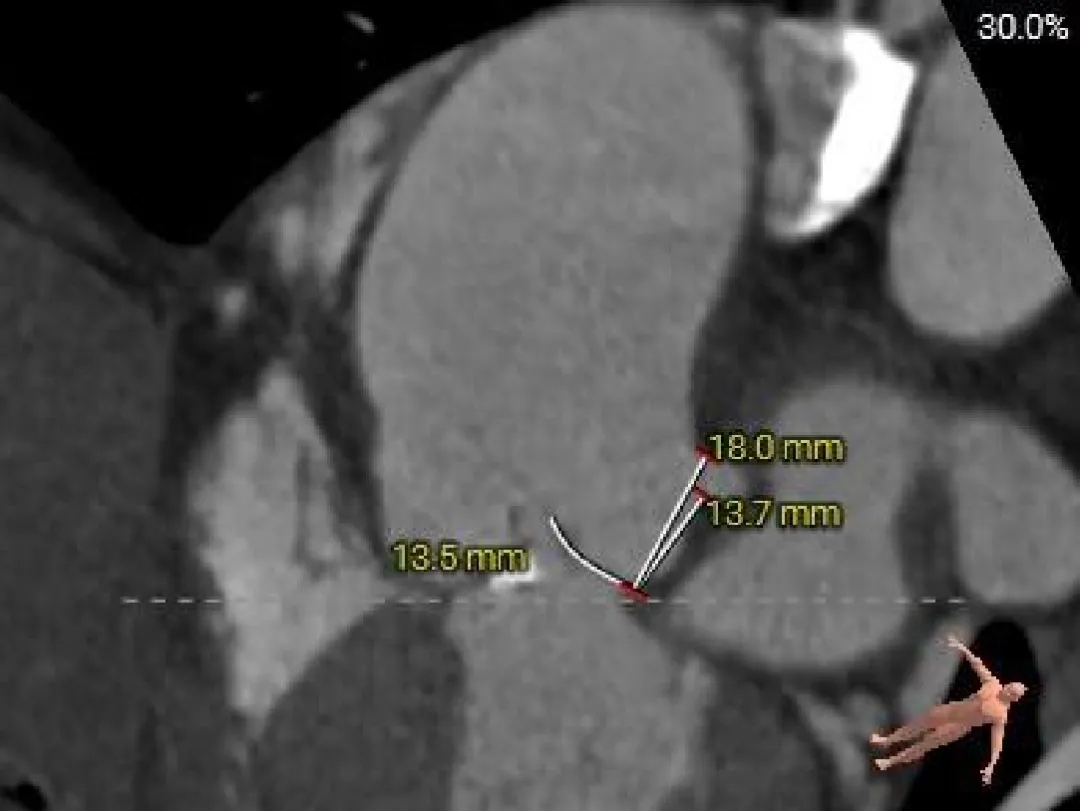

冠脉风险评估

Left Coronary

LCA & Leaflet

Right Coronary

RCA & Leaflet

左、右冠脉高度尚可

双侧瓣叶不长

结合SOV、STJ内径评估冠脉风险不高